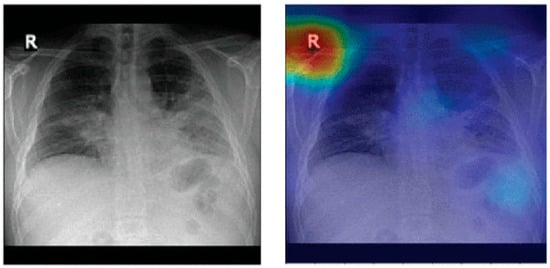

8.1. Biased Datasets

It has been shown that pneumonia detection models tend to focus on irrelevant features when classifying CXR images. A detailed bias analysis has been presented in [121]. The classification network used in that study was VGG16 [196]. The network was pretrained on an ImageNet dataset [197], and then, using transfer learning, the network was trained and fine-tuned on domain data. Figure 12 depicts some CXR images that were fed to the model. The figure also shows the corresponding heatmaps generated using Grad-CAM [198]. The heatmaps highlight areas of the image that are critical in the model’s prediction. It can be seen that for both the generated heatmaps in Figure 12, the highly activated regions (denoted in red) are outside the boundaries of the lung tissue. This indicates that features of the lung tissue have not been utilized in the classification decision. The study [121] suggests that this behavior demonstrated by the classification models is due to the inherent biases present in the publicly available pneumonia and COVID-19 CXR image datasets [31,34,158].

Figure 12.

Lung heatmaps generated through Grad-CAM (all images taken from [121]).

These dataset biases could be due to a variety of reasons. An example scenario which can lead to such biases is when a specific CXR machine is used for a group of subjects with a lower chance of disease and a separate CXR machine is used for another group of subjects with a high chance of disease. This may happen when patients highly suspicious of a contagious disease, like COVID-19, are sent to some other area of hospital or even to some other healthcare center for CXR scanning in order to avoid spreading the disease. If one of the two machines generates a white rectangular box at the top right corner in each CXR image and the other one does not, then the model may learn to classify images based on this simple feature rather than true class features.

Another possible scenario is that there is an imbalanced dataset; i.e., there are too few images for one class and a lot more for the other class, e.g., too few COVID-19 CXR images and much more normal CXR images. In order to balance the dataset, COVID-19 samples are included from different data sources. Each of these data sources is likely based on different equipment as well as acquisition protocols. In other words, the samples of the two classes are from different sources. Therefore, the resulting dataset is inherently biased. Any classifier trained on such a dataset may learn to classify CXR images based on source-specific features rather than true class features.